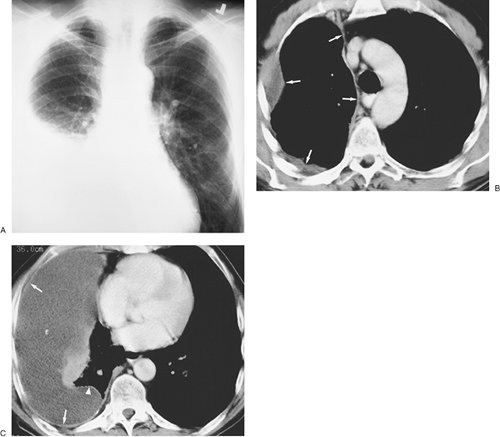

FIGURE 9-3. Subpleural squamous cell bronchogenic carcinoma. A: Posteroanterior (PA) chest radiograph of a 67-year-old woman shows a mass in the left upper hemithorax (arrows) that is contiguous with the pleural surface. B: CT with lung windowing shows the mass abutting the lateral pleural surface and major fissure. C: CT with mediastinal windowing shows that the mass is contiguous with the pleural surface. Centrally, the mass contains areas of low attenuation, consistent with necrosis.